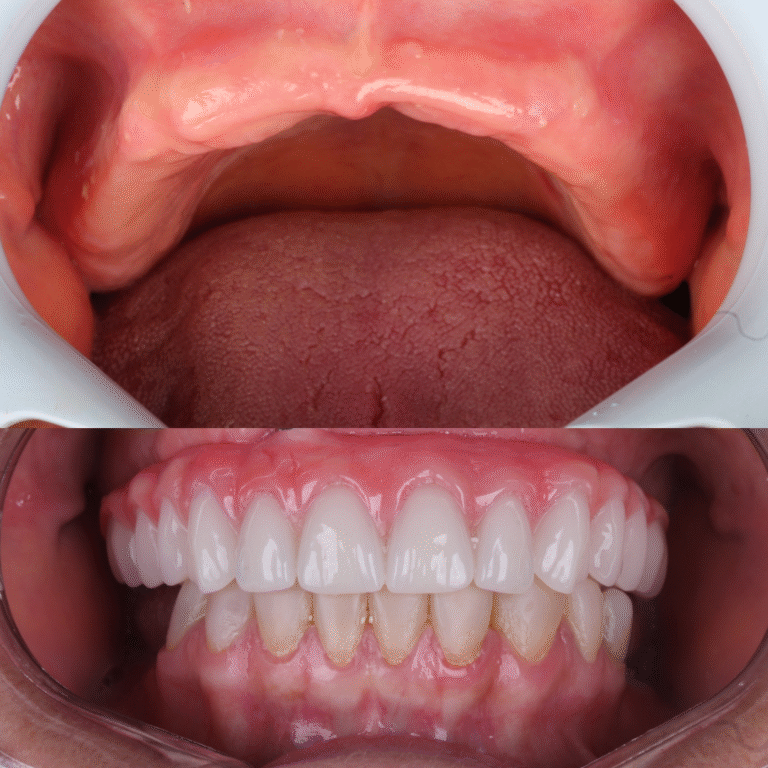

Veja alguns dos resultados obtidos através dos nossos tratamentos especializados.